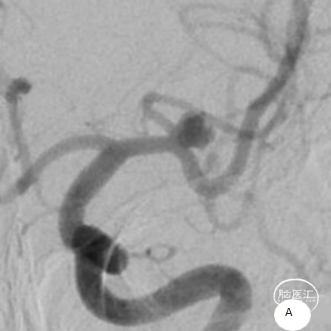

术前造影

患者推入放射科导管室平躺于检查床上,常规心电、血压监护;消毒右侧腹股沟区,铺手术巾,气管插管全身麻醉后,穿刺右侧股动脉,置入导管鞘,成功后置入超滑导丝及椎动脉导管,行左侧颈内动脉3D造影术,明确动脉瘤栓塞和辅助支架置入的工作体位。

载瘤动脉细小,经测量为0.87mm,角度为反向角度,释放支架易贴壁不良,颈内动脉段血管入路较迂曲,需要支撑力及柔顺性较好的微导管,同时避免微导管拉直血管并使血管位移而影响定位。